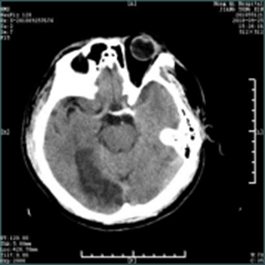

急性脑梗死的教学案例 专业知识 脑梗死(cerebral infarction,CI)又称缺血性脑卒中,是指各种原因所致脑部血液供应障碍,导致脑组织缺血、缺氧性坏死,而出现相应神经功能缺损的一类临床综合征。 案例 孙某,男,主因“发现言语不清、左侧肢体活动不灵1小时10分”入院。患者于14:30左右起床时发现言语含糊不清,吐字费力,口角歪斜,左侧肢体活动不灵,表现为左上肢无法抬起,左下肢无法行走,伴头晕,视物不适,无头痛,无恶心、呕吐,无视物旋转,无一过性黑矇,无意识障碍,无胸闷、气短。为求进一步诊治急来我院就诊。患者今日中午13:30睡午觉时无言语不清,无左侧肢体活动不灵。既往高血压病史10年余,平素血压最高达 210/120mmHg,未规律系统用药;否认心脏病、糖尿病病史。 查体:体温:36.5℃,血压:163/100mmHg,呼吸:20次/分,双肺呼吸音清,心率89次/分,腹软,双下肢无浮肿。神经系统查体:意识清,构音障碍,左侧瞳孔大约5.0mm,右侧瞳孔大约3.0mm,对光反射灵敏,水平眼震,左侧同向性偏盲,右侧头面部麻木,右侧周围性面瘫,伸舌居中,左上肢近端肌力2级,远端肌力2级;左下肢近端肌力3-级,远端肌力3-级,右侧肌力5级,四肢肌张力正常,腱反射(++),左侧Babinski(+),颈软,克氏征(-),NIHSS评分:9分。急查头部CT示:右侧枕叶低密度影。

立刻按静脉溶栓准备给予采血、心电、血压、血氧监护、吸氧。考虑患者为缺血性卒中,发病在溶栓时间窗内,但右侧枕叶低密度考虑为近期梗塞,静脉溶栓有一定出血风险,与患者家属沟通病情,交代溶栓利弊、告知可能出现的风险及预后。征得同意后给予静脉溶栓治疗(DNT:40min)。进一步行多模CT检查,发现患者椎基底动脉存在明显狭窄,建议溶栓后行桥接动脉取栓,患者家属拒绝。溶栓后患者肢体力量较前好转,溶栓24小时后给予抗血小板聚集、调脂稳斑、改善循环治疗,监测并控制血压。病情稳定后康复锻炼。出院时患者一般状态较前明显好转,左侧同向性偏盲,右侧头面部麻木,左侧肢体肌力5-级,右侧肌力5级。NHISS评分:2分,生活能够自理,对患者进行卒中二级预防教育,后随访患者预后良好。 脑梗死是神经科常见病,起病急骤,尤以后循环梗死病情凶险。神经系统体格检查对定位诊断具有重要意义,辅助检查DWI、MRA、CTA、DSA可以明确梗死部位、责任血管,对治疗方案确定、判断患者预后意义重大。 脑梗死急性期治疗包括静脉溶栓及动脉取栓,需根据患者病情严重程度及经济条件选择合适治疗方法,向患者及家属告知最优的治疗方案、提前预判可能出现的问题是一个合格神经科医生的责任,而合理有效的沟通是前提。 通过本案例学习,使学生掌握脑梗死引起神经功能缺失的表现,回顾神经解剖,了解神经系统查体的重要性,通过给出患者CT及MRI的结果,识别早期脑梗死的影像表现,了解脑血管的解剖,学习椎基底动脉系统梗塞的表现。拓展静脉溶栓及桥接治疗的意义及风险。 融入的思政教育元素 树立以病人为中心和以人为本的理念;注重医患沟通,根据患者经济情况选择合适的治疗方法;注重团队合作;提高对卒中的认识。 选择脑梗死作为PBL讨论课,因为它给人类健康造成严重危害,致残、致死率高,给患者及其家庭带来沉重的负担。通过此案例旨在让医学生了解处理急性脑梗死病人时要以同理心对待,把“时间就是大脑”牢记心间,注重团队合作精神,通过与急诊科、影像科、检验科、康复科等通力合作,共同挽救患者生命。 静脉溶栓及桥接治疗均存在一定风险,作为医学生应当了解可能的风险,提前判断预后,与患者家属沟通时,掌握沟通技巧,提前告知可能出现的风险,重要决定前需签署知情同意书,当患者拒绝有风险处置时应尊重患者意愿。静脉溶栓或桥接等治疗方案需要考虑患者经济条件及患者意愿。 2020年10月29日是第15个世界卒中日,今年宣传主题是“医体融合,预防卒中”,口号是“科学运动,健康生活”。在人文方面探讨卒中的预防,倡导运动与医学防治相结合,更好地防治卒中,高科技提供生活便利的同时,让人们的体能运动大大减少,而生命在于运动,“四体不勤”势必会给健康带来隐患。运动作为预防卒中、强身健体的良好预防方式,人人皆可行,这与健康中国行动计划不谋而合。推动体育与全民健身加入,预防卒中的行动是世界卒中组织的呼吁,也是中国政府的要求。重视医体融合预防,以实际行动实现健康中国的伟大梦想。 |